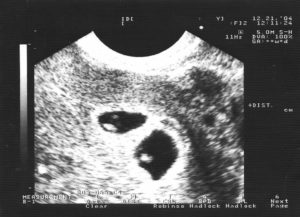

При одноплодной беременности на снимке различают темное околоплодное яйцо, которое имеет четкие, ровные границы и круглую или овальную форму. Его размер – 10 мм.

В плодном яйце заметен крошечный эмбрион (2–3 мм). На снимке он представляет собой пятно, напоминающее креветку или запятую, более светлого цвета. Если присмотреться, на картинке заметен желточный мешок (более темное пятно размером 4–6 мм) и не до конца сформировавшийся кишечник без характерных извилин.